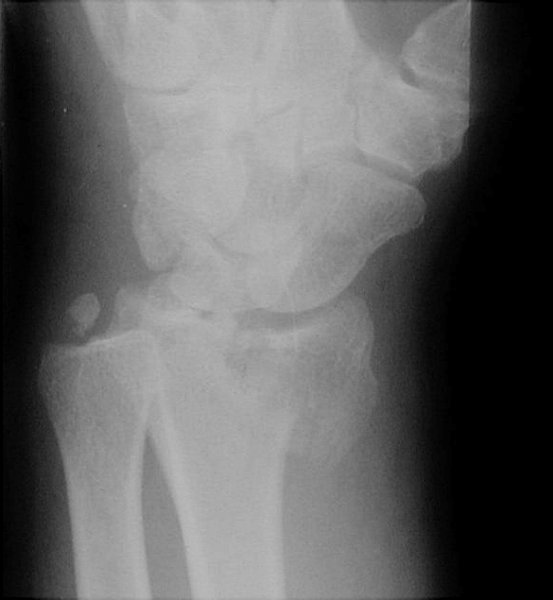

Return to Reverse Barton Fracture